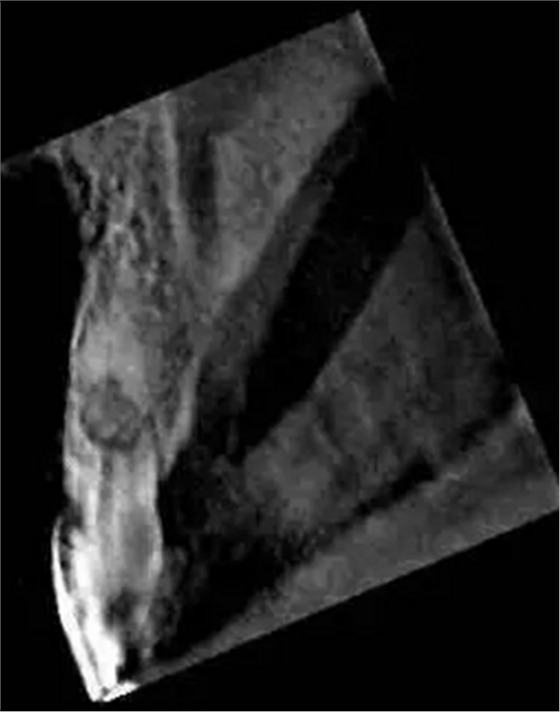

左上中切牙近遠中有牙色充填體,邊緣繼發(fā)齲,牙齒不松動,輕微叩痛,患牙冷測遲鈍,牙齦未見異常。X線片示:充填體周圍繼發(fā)齲壞近髓,根中部大面積低密度影,蟲噬狀,內(nèi)部結構顯示不清晰,根尖周未見異常。錐形束CT(CBCT)顯示根中部內(nèi)吸收多處可疑穿孔,缺損內(nèi)可見菜花狀鈣化物影像

近期研究和病例報告均顯示CBCT有助于牙根吸收病例的診斷[3, 6, 13]。本病例中使用CBCT判斷缺損大小、內(nèi)容物形狀和根管壁可能側穿孔的位置,起到了輔助診斷治療的作用。